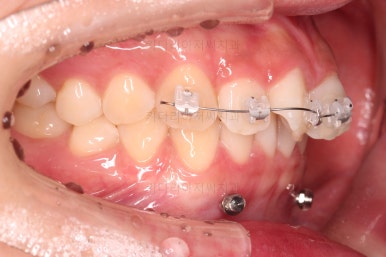

이번 환자분이 사용한 장치는 엠파워 클리어라고 하는 자가결찰 세라믹 장치입니다.

일반적으로 클리피씨라고 많이 알고 계시는 장치가 "자가결찰 세라믹" 종류이며 여러 종류 중 엠파워 클리어도 있습니다.

제조사만 일본(클리피)이냐 미국(엠파워)이냐의 차이입니다.

아래 앞니는 브라켓보다는 훨씬 작은 미니튜브 장치를 사용했습니다.

과개교합의 경우 브라켓을 부착하게 되면 씹히게 되어 치료과정이 수월하지 못하기 때문이죠.

중간중간 미니스크류가 빠지든, 위치적으로 좋은 곳을 선택하든 여러 이유로 미니스크류 재식립이 몇 번 있었고요.

부족한 공간은 치간삭제를 통해서 만들어 나갑니다.

디테일을 위해서 윗니는 어금니에도 하나씩 장치를 더 부착했고, 아랫니는 바로 뒷 치아에도 장치를 부착했습니다.